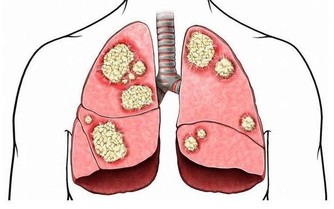

丑時肝經最旺,丑時(1:00—3:00)不眠,肝無法解除掉有毒之物,產生新鮮血液,因藏血不利,面呈青色,久之易患各類肝病。乙肝病毒攜帶者,是由於晚上經常不睡覺,人太虛弱了,也就是說秩序太亂了,病毒已經到了細胞裡了。